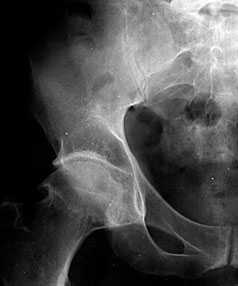

В начальных стадиях (1–2 стадии по Kellgren) ОА тазобедренных суставов при рентгенологическом исследовании определяются: незначительное сужение суставной щели, слабовыраженный субхондральный остеосклероз, точечные кальцификаты в области наружного края крыши вертлужной впадины (зачаток остеофитов), заострение краев ямки бедренной головки в области прикрепления круглой связки бедренной головки (рис. 1).

Рис. 1. Обзорная Rо-графия тазобедренного сустава в прямой проекции.

Деформирующий остеоартроз II ст. по Kollgren. Крупные остеофиты на краях суставных поверхностей. Грибовидная деформация бедренной головки

В поздних стадиях заболевания (соответствует 3–4 стадии ОА по Kellgren) отмечаются:

• прогрессирующее сужение суставной щели

• формирование различной формы и размеров остеофитов на краях суставных поверхностей вертлужной впадины, бедренной головки, отчего она со временем приобретает грибовидную форму. В средней части вертлужной впадины возможно формирование клиновидного остеофита, который может обусловить латеральное смещение бедренной головки

• углубление вертлужной впадины может быть связано с развитием остеофитов; протрузия ее возможна на фоне остеопороза или истончения костей, составляющих дно вертлужной впадины

• выраженный субхондральный остеосклероз. Проявляется в первую очередь в области крыши вертлужной впадины, затем в верхнем отделе бедренной головки

• в далеко зашедших случаях – уменьшение в объеме и уплощение суставной поверхности бедренной головки на фоне выраженной кистовидной перестройки костной ткани, чередующейся с участками субхондрального остеосклероза. Костные кисты могут быть единичными или множественными. Возникают они в верхней части вертлужной впадины или в зоне наибольшей нагрузки на суставную поверхность бедренной головки

• асептический некроз бедренной головки

• подвывихи бедренной кости чаще вверх и латерально, реже вверх и медиально

• уплотнение костной ткани и укорочение шейки бедренной кости.